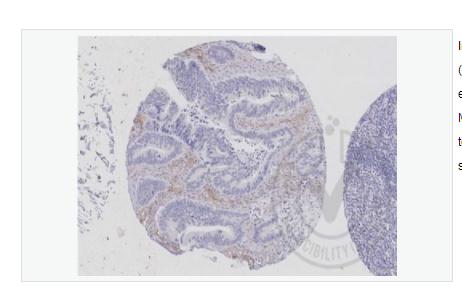

WB=1:500-2000 ELISA=1:5000-10000 IHC-P=1:100-500 IHC-F=1:100-500 IF=1:100-500 (石蜡切片需做抗原修复) not yet tested in other applications. optimal dilutions/concentrations should be determined by the end user.

Applications:WB(1:500-2000)

ELISA(1:5000-10000)

IHC-P(1:100-500)

IHC-F(1:100-500)

IF(1:100-500)